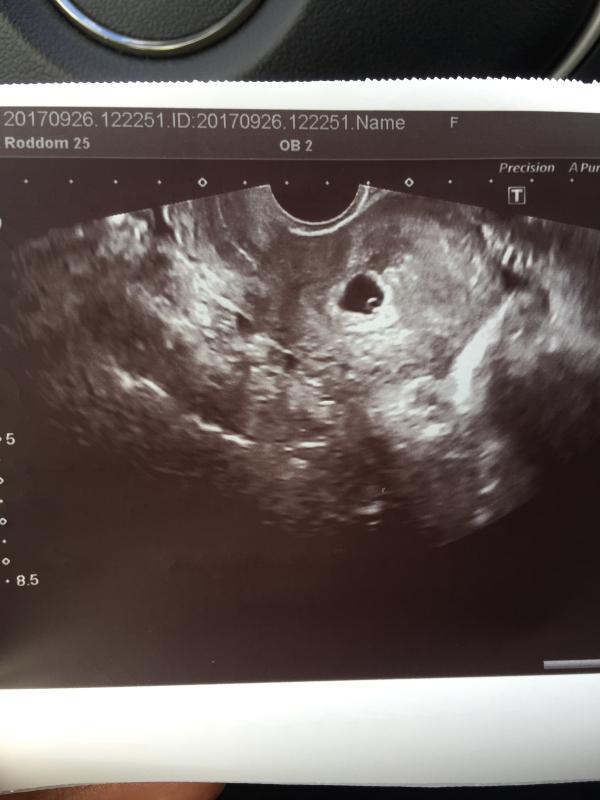

@albinochka_tretyakova, @missz, считают по размерам пя) когда у меня было пя 5мм поставили срок 3 недели )

3см -10,5 недель )(если правильно помню)

Эмбриональный - смотрят размер пя(на ранних сроках)

@albinochka_tretyakova, ну эмбриона еще не видно, через пару недель должен появится)

Маааленькая кнопочка :))) Буквально на днях собирала все свои документы в кучу, нашла первое узи. Такая же кнопка была. Смотрю вниз...на пузо, а там уже пупок торчит :))) Так быстро время летит. :))) здоровья вам :))